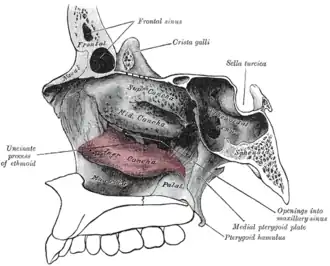

Figure 1: Lateral wall of right nasal cavity showing inferior concha in situ. (pink) | |